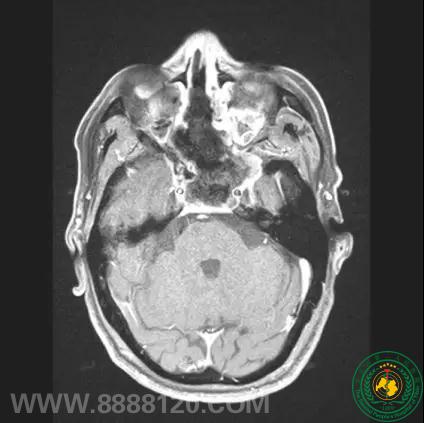

神经外一科完成四川省第一例经鼻神经内镜下蝶窦脑膜瘤切除术

神经外一科完成四川省第一例经鼻神经内镜下蝶窦脑膜瘤切除术18028